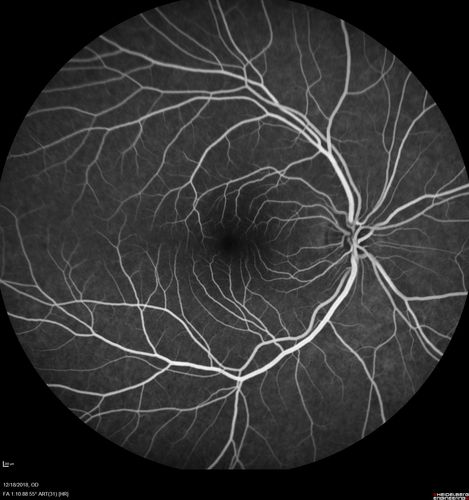

White Retinal Artiole Left eye - Inferotemporal

31 year old female with migraines and headaches for the last 12-13 years. Sometimes she gets the visual symptoms with the migraine. When she gets the migraines the pain is on the left side of her head. She gets the problem a few times a month, sometimes more. They usually last 5-6 hours. She has not had a permanent vision change. When she gets a vision change there are spotty dots of blue neon lights in her vision. With her glasses her two eyes are about the same. VA 20/16 in Each Eye